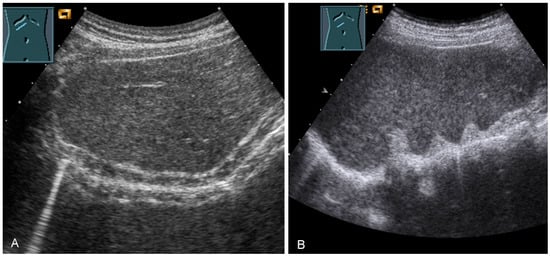

Border shadow artifacts may indicate an apparent diaphragmatic gap, which disappears when the transducer position is changed (Figure 30).

Figure 30.

Illustration of artifact-related apparent diaphragmatic rupture (A, arrow) with regular findings and slightly lateral sound propagation to the diaphragm (B).